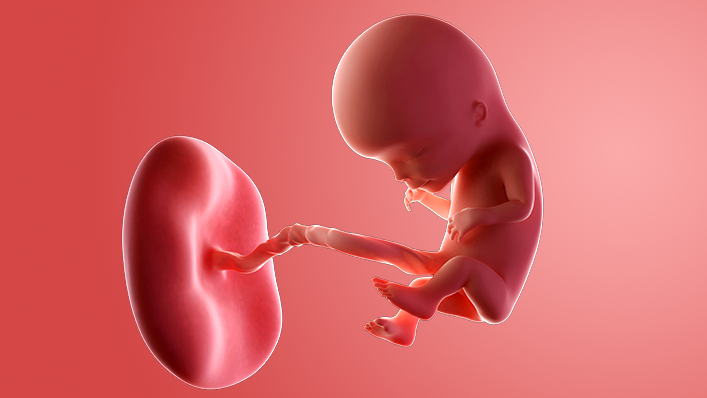

Your baby, or foetus, is now around 30mm long from head to bottom, which is about the size of a small apricot.

The baby will be making jerky movements and baby's movement can be seen on a scan.

Your baby is going through another huge growth spurt. The head is still too big for the body, but the face is more recognisably in proportion. The eyes are half closed but can react to light.

The ears are starting to form, the mouth now has a delicate upper lip and the nose has 2 little nostrils. The jaw bone is shaping up too, and contains tiny versions of your baby's milk teeth.

The heart is beating extremely quickly at 180bpm – that's about 3 times your heart rate.